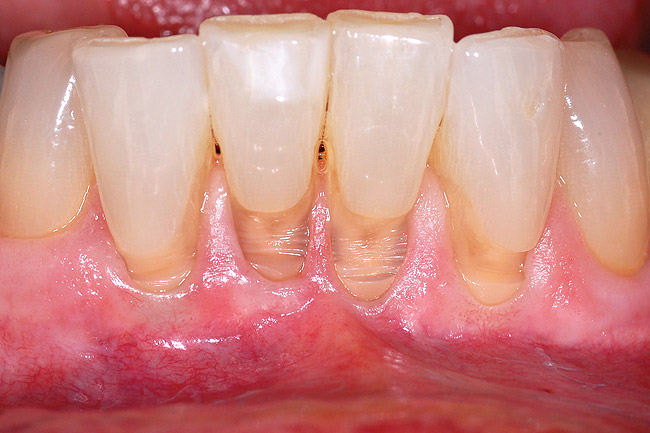

Fig 1 and Fig 2. Non-carious cervical lesion on the root surface of a maxillary canine. There was no attached gingiva, the cervical lesion was less than 2 mm in depth, and the recession was Miller Class I.

Figure 2